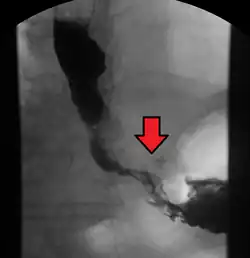

Although an occlusive tumor may be suspected on a barium swallow or barium meal, the diagnosis is best made with an examination using an endoscope. This involves the passing of a flexible tube with a light and camera down the esophagus and examining the wall, and is called an esophagogastroduodenoscopy. Biopsies taken of suspicious lesions are then examined histologically for signs of malignancy.

-

Endoscopic image of Barrett esophagus – a frequent precursor of esophageal adenocarcinoma -